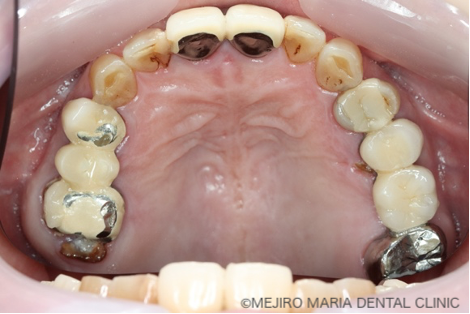

患者様は、長年にわたり臼歯部(奥歯)の噛み合わせの調子が悪いことと、食事の際に痛みを感じることを主訴に来院されました。前歯部から口腔内を確認すると大きなトラブルは確認できませんが、レントゲン撮影と口腔内診査を行うと、多数の臼歯部の歯牙(歯)が歯根破折により抜歯を余儀なくされる状況でした。

まずは、歯周組織検査を含めた口腔内診査、レントゲン写真の撮影により、保存できる歯牙と、抜歯をせざるを得ない歯牙などを選定しました。

今回の症例では、歯根破折していた5本の歯牙(下の写真・赤矢印)に対して、抜歯を提案した。また、診断用WaxUp(ワックスアップ)を行ったところ左下のブリッジ(青丸)と右下(青矢印)の噛み合わせ平面が乱れており、咬合に負担をかけていることが予想されました。そのため、最終的にそれらの不調和を改善し、適切な噛み合わせにすることをゴールとして治療を開始しました。